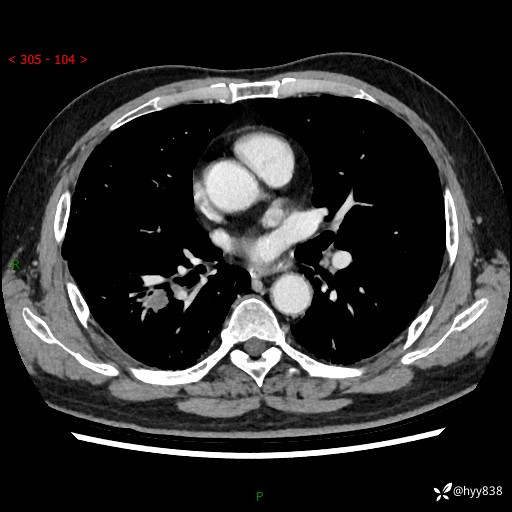

71岁/男,咳嗽伴气促半月。一年前肺手术史,又见两个结节,穿刺结果意外---结果公布~

【现病史】:患者半月前无明显诱因出现咳嗽、咳痰,为白色粘痰,无明显加重与缓解因素,伴气促,无发热,无大量脓痰,无胸痛、咯血,无哮鸣音,到我院就诊,胸部CT示右肺结节增大,并口服药物治疗无明显好转,具体用药不详,为求进一步治疗随来我院,经门诊以“孤立性肺结节”收入我科。 病程中患者精神、饮食可,睡眠不佳,大小便正常,体力下降,体重未见明显下降。

[既往史]:2022-06于当地第一人民医院确诊慢阻肺,现规律使用杰润(1次/日);2023-04-06于当地市第一人民医院行胸腔镜右肺上叶楔形切除术+右肺上叶切除术+淋巴结清扫术+胸膜黏连松解术,确诊为右肺鳞癌 pT2aN0M0 Ib期

【检查】:胸部CT平扫+增强